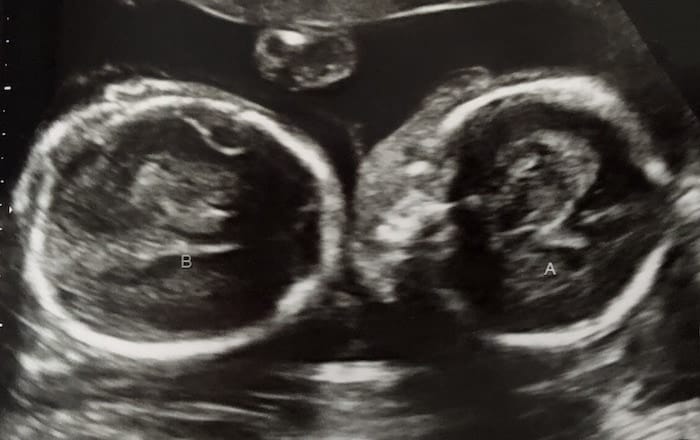

Ultrasound Photos at 21 Weeks Pregnant With Twins